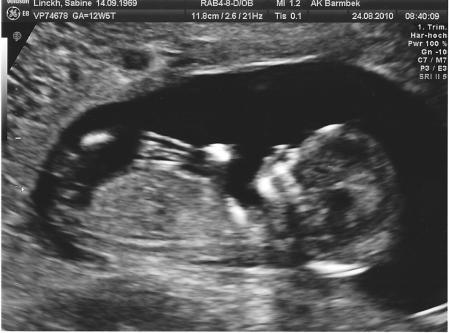

hatte letzte Woche eine wirklich stressige Woche, so daß ich gar nicht dazu gekommen bin von der Nackenfaltenmessung zu erzählen....und natürlich das dazugehörige Foto zu zeigen...

Es war - wie Claudia schon sagte - ein absoluer Luxus den kleinen Zwerg so lange beobachten zu dürfen. Bei mir war es besonders drollig daß er sich nicht von Drehen wollte, trotz leichter Stupsbewegungen der Ärztin - tja ist wohl ein frühes Anzeichen von eigenwilligem Charakter....

Die Werte sind, so die Ärztin, sehr gut - die Wahrscheinlichkeiten die einer 30 jährigen (ich werde in 2 Wochen 41) und so habe ich mir den Bluttest gespart um mich nicht noch zu beunruhigen....

Ach ja die Daten ... also was ich noch weiss ist die Steisslänge von 7,3 cm...